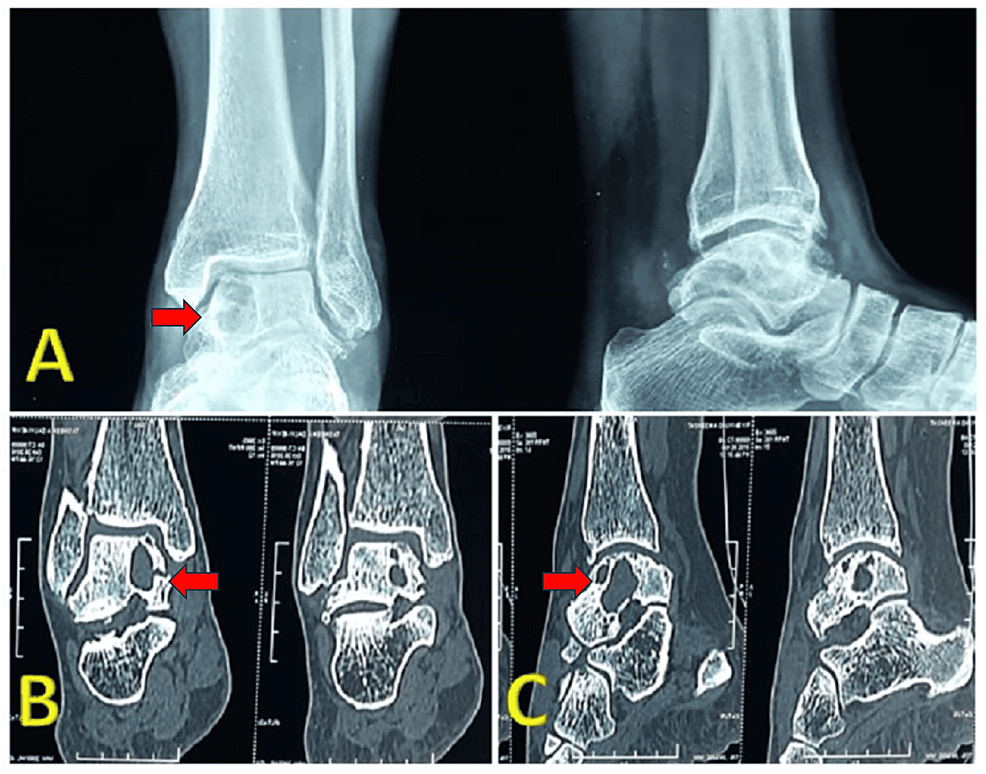

Axial and sagittal CT scans confirm fragmentation of the tarsal Talus Bone Cystic Lesion Point loading and loose bodies cause a synovitis, and the mechanics of the joint. Osteochondral lesions of the talus (olt) remain a challenging pathology for the foot and ankle surgery community from diagnosis to. Each stage is defined as follows: Large bone cyst of the talar body frequently is associated with an osteochondral lesion (ocl). 1 it can be developed. Talus Bone Cystic Lesion.

Anteroposterior (A) and lateral (B) radiographs of the right ankle show Talus Bone Cystic Lesion Large uncontained lesions are usually painful as the structure of the talus is threatened. 1 it can be developed by the valve mechanism of the damaged. Osteochondral lesions of the talus (olt) remain a challenging pathology for the foot and ankle surgery community from diagnosis to. Each stage is defined as follows: Large bone cyst of the talar body frequently. Talus Bone Cystic Lesion.